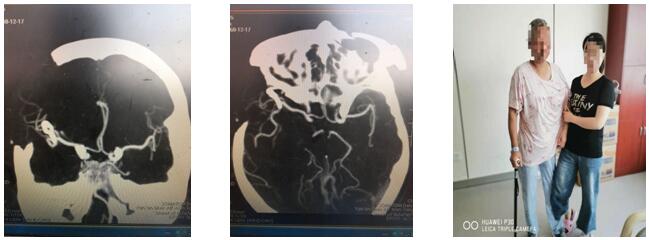

此时患者已经陷入深昏迷,情况紧急,时间就是生命,已经没有再多的时间考虑了,科主任刘小雷、责任总医师游文良再次组织全科医师讨论,详细向家人告知目前情况,最终决定急诊开颅手术。如何避免术中发生大出血,成为摆在神经外科二病区团队面前的最大问题。刘小雷主任,游文良责任总医师带领的神经外科团队经过慎重、反复讨论,决定由翼点入路夹闭动脉瘤并清除血肿。手术在全麻下进行。首先要通过脑自然间隙找到大脑中动脉下干,仔细分离,暴露动脉瘤,予以夹闭。整个过程都必须经过脑自然间隙进入颅脑深部,保证脑组织、血管和神经的完好,最后清除血肿,血肿腔严密止血。手术圆满完成。目前患者处于恢复期,患者神志清,言语流利,思维清楚,除左侧肢体肌力稍减弱外,其他功能均正常,在家人搀扶下可以慢慢行走。